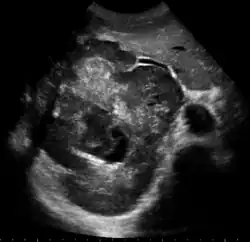

![]() Rak wątrobowokomórkowy u pacjenta z marskością wątroby na podłożu WZW C | |